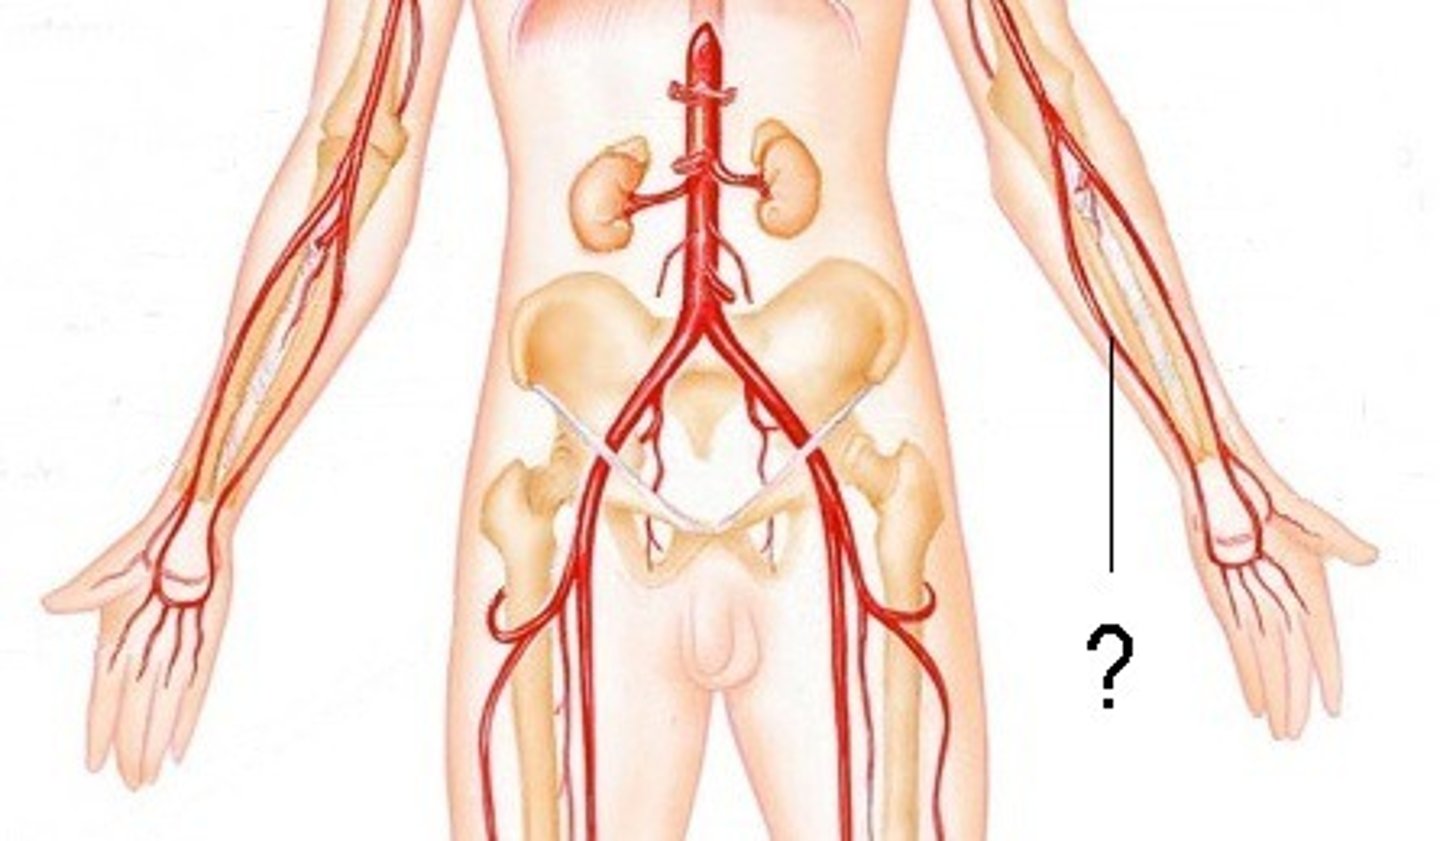

radial artery

serves the lateral forearm, wrist, thumb, and index finger

ulnar artery

serves the medial forearm and digits 2-5